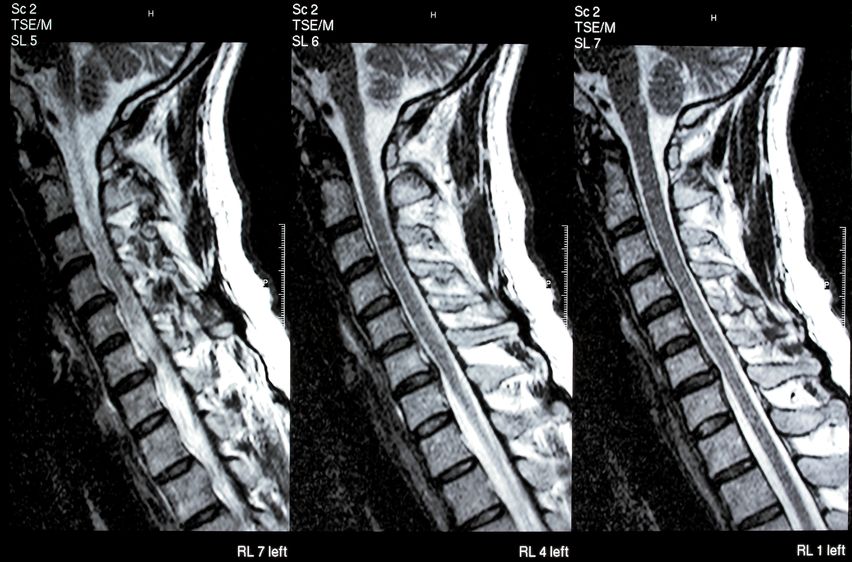

I am currently recovering from neck surgery for a bulging disc between c5 and c6. The procedure was called a ACDF- an anterior cervical discetomy where the surgeon makes an incision in the front of your neck off to the side, to get to the disc. He then replaces the disc with a piece of special plastic that dissolves as the bones start to heal and graft.